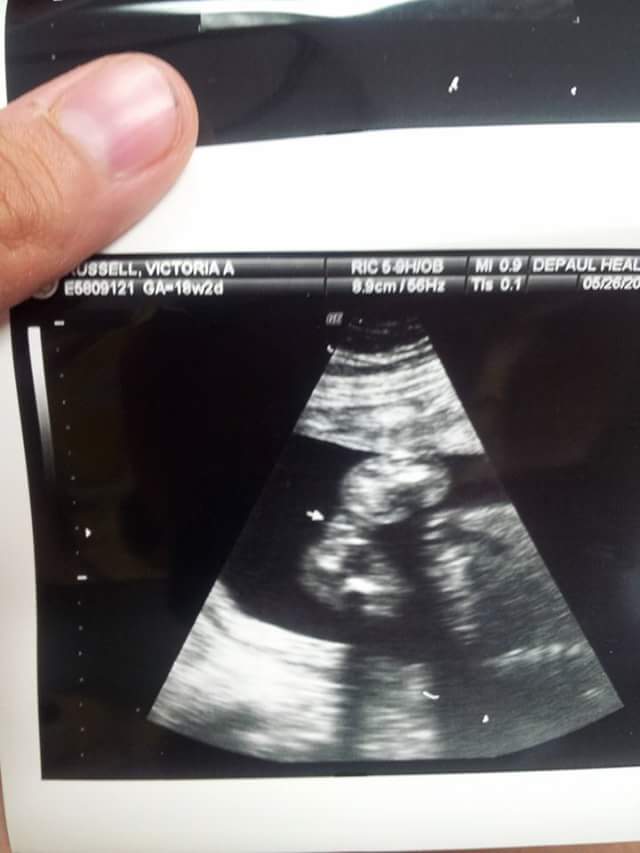

this was my 18 week scan... tech said she thinks girl but could be boy but not very likely.